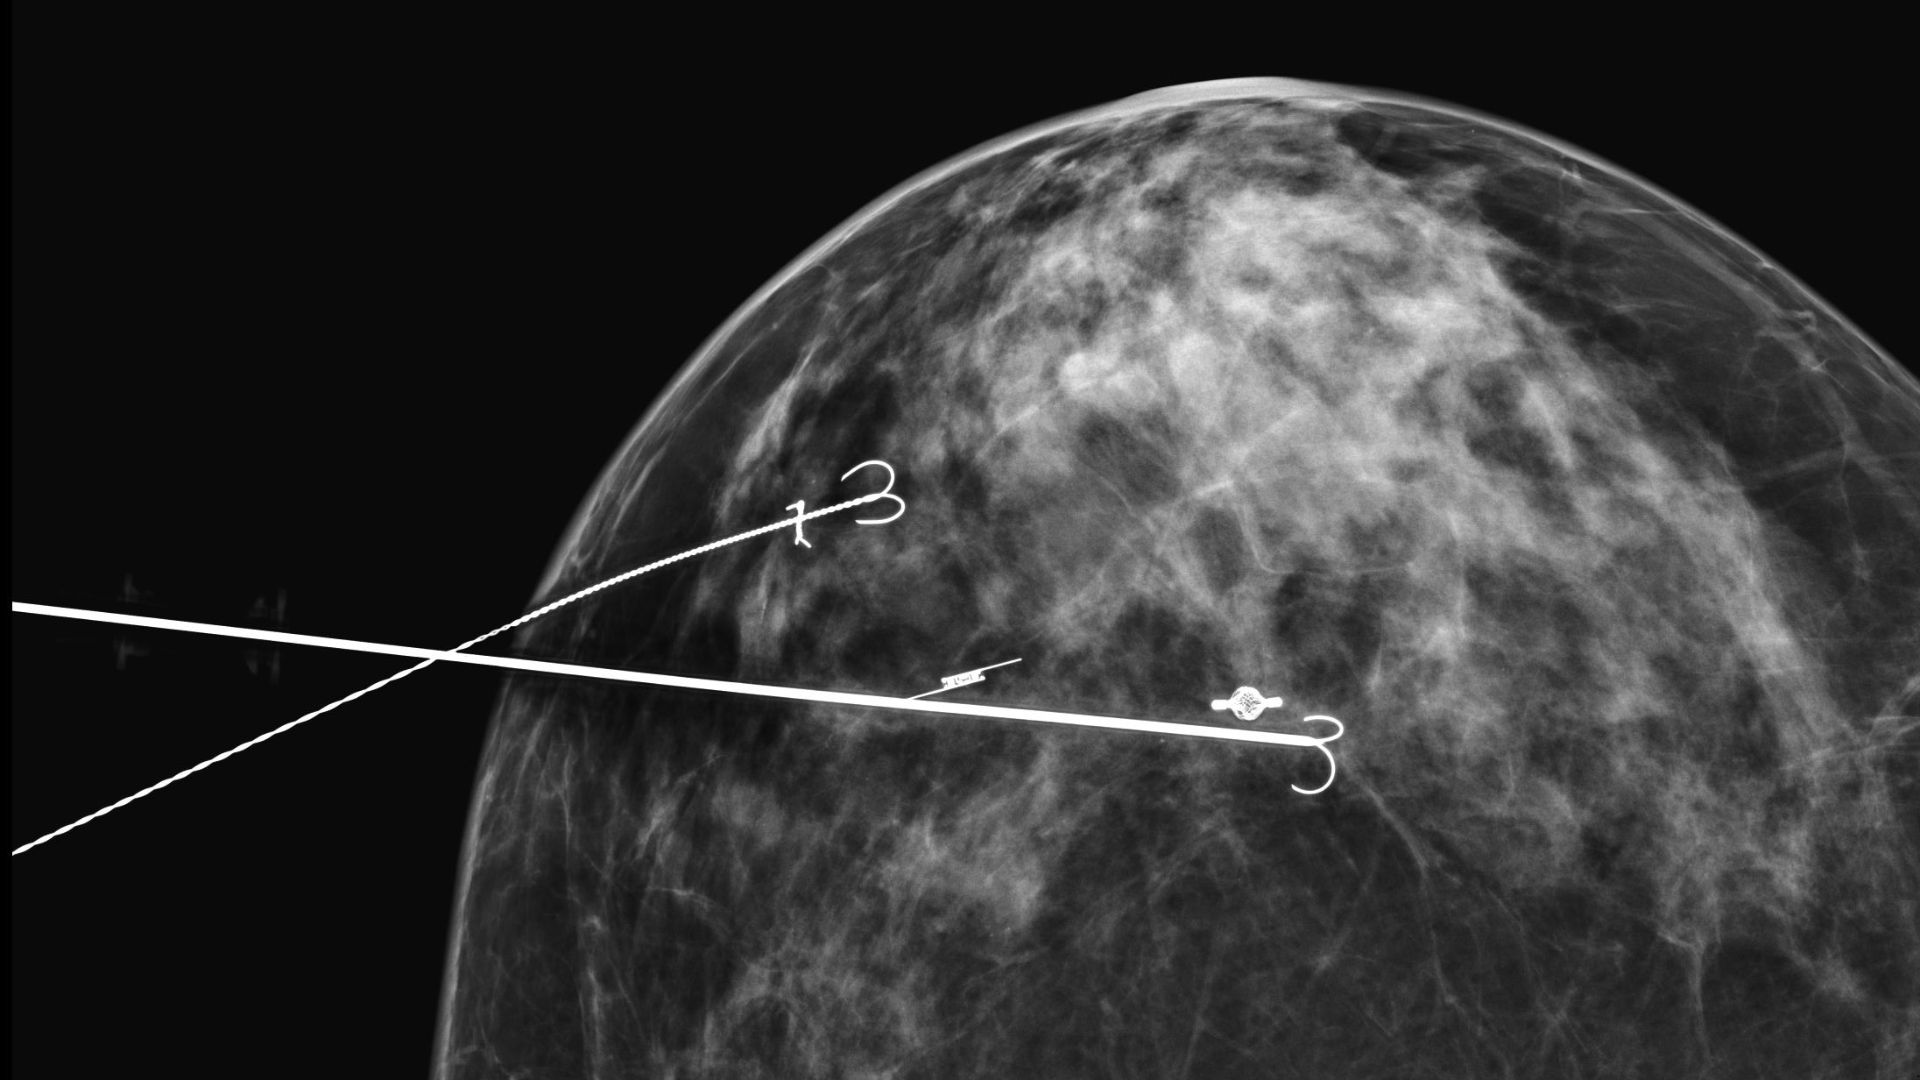

El marcaje o localización prequirúrgica es un procedimiento en el que se colocan una o más agujas o arpones en la zona del pecho donde se encuentra la lesión. Se llama “arpón” porque tiene un sistema especial que lo fija al pecho para que no se mueva una vez colocado. Esto ayuda al cirujano a encontrar y extirpar la lesión con precisión.

Primero, tendrás que firmar un consentimiento informado. Para localizar la lesión, se puede utilizar un ecógrafo (un ecógrafo es un dispositivo médico que utiliza ondas sonoras de alta frecuencia para crear imágenes de los órganos y tejidos del cuerpo) o un sistema especial con el mamógrafo (estereotaxia), que comprime el pecho. Una vez colocado el arpón, puede ser necesario hacer una mamografía para asegurarse de que está en el lugar correcto.